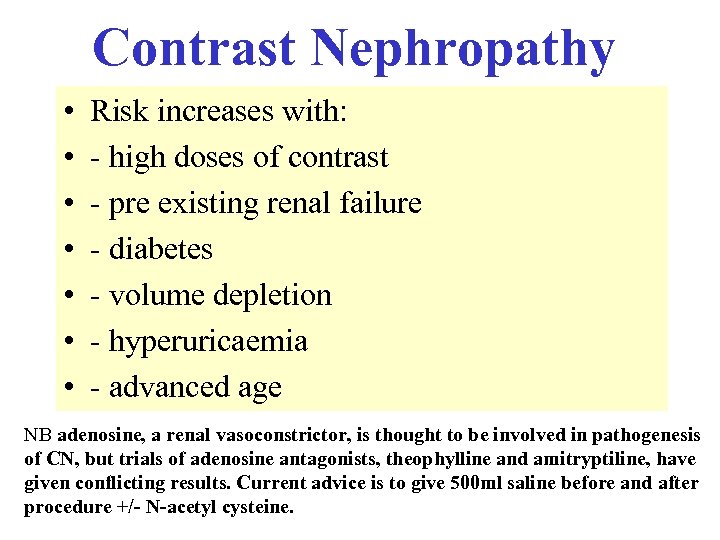

Contrast Nephropathy • • Risk increases with: - high doses of contrast - pre existing renal failure - diabetes - volume depletion - hyperuricaemia - advanced age NB adenosine, a renal vasoconstrictor, is thought to be involved in pathogenesis of CN, but trials of adenosine antagonists, theophylline and amitryptiline, have given conflicting results. Current advice is to give 500 ml saline before and after procedure +/- N-acetyl cysteine.

Contrast Nephropathy • • Risk increases with: - high doses of contrast - pre existing renal failure - diabetes - volume depletion - hyperuricaemia - advanced age NB adenosine, a renal vasoconstrictor, is thought to be involved in pathogenesis of CN, but trials of adenosine antagonists, theophylline and amitryptiline, have given conflicting results. Current advice is to give 500 ml saline before and after procedure +/- N-acetyl cysteine.